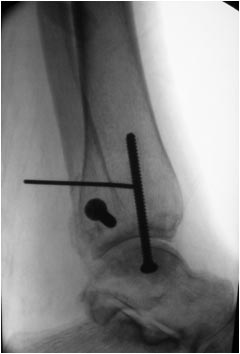

Мне кажется, что вопрос, поставленный Вами: "Возможно ли одномоментно устранить подвывих или только на аппарате Иллизарова?", отражает не совсем ясное понимание ситуации. Что значит устранить подвывих? А пластику ложных суставов внутренней лодыжки и заднего края большеберцовой кости не нужно делать? И ось голеностопного сустава нужно исправлять. То есть делать остеотомию наружной лодыжки (если она срослась, по снимку не очень понял). Артродез голеностопного сустава в такой ситуации очень сложен. Если же добиться сращения всех переломов в правильном положении, артродез вполне можно отсрочить на несколько лет, что для молодого пациента достаточно важно. Но в конечном счете все определяется Вашим умением и ясным представлением того, чего Вы хотите добиться своей операцией. Во вложении - в чем-то похожий случай. Оперировал эту пациентку 23 лет 11 лет назад через 8 месяцев после похожего на представленный Вами остеосинтез. На первой операции перелом малоберцовой кости в нижней трети был просто не замечен. За счет восстановления оси быстро развившийся артроз протекал благоприятно. В результате артродез был выполнен только в прошлом году, через 10 лет после второй операции. И боли беспокоили пациентку только в течение года перед артродезом.